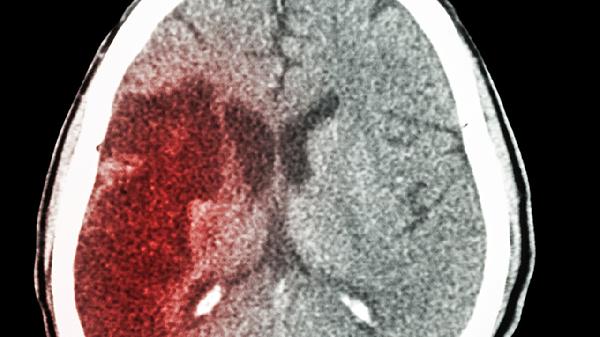

某些腦血管疾病,如腦梗死或腦出血,也可能是導致暈倒的原因。因為這些疾病會(huì )影響大腦的供血和供氧,可能導致意識短暫?jiǎn)适?。遇到這種情況,及時(shí)到醫院進(jìn)行詳細檢查是非常重要的,以便醫生能夠根據具體情況進(jìn)行治療。